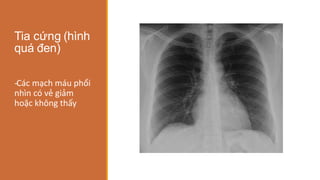

Tia cứng (hình

quá đen)

-

‐Các mạch máu phổi

nhìn có vẻ giảm

hoặc không thấy